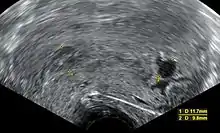

![]() | |

| An ultrasound showing a gestational sac containing a yolk sac but no embryo | |